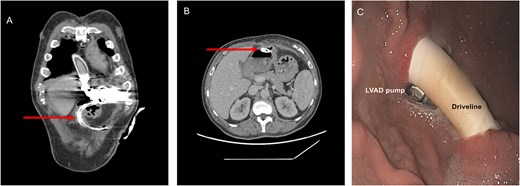

The obtained blood cultured revealed the presence of S. anginosus. As infectious parameters were persistently elevated after empirical antibiotic treatment escalation to piperacillin/tazobactam with no specific clinical focus, a computed tomography (CT) scan was performed revealing free intra-abdominal air and an intragastric transposition of the LVAD-DL (Fig. 1A and B). This was confirmed by esophagogastroduodenoscopy, which revealed a short-range intragastric course of the DL with its entry and exit sides, as well as visible components of the pump (Fig. 1B and C). Next to the intragastric DL, a gastric ulcer measuring ~10 mm was identified.

Preoperative CT scan (A, B) and esophagogastroduodenoscopy (C) revealing intragastric DL transposition. The arrow points at the DL.